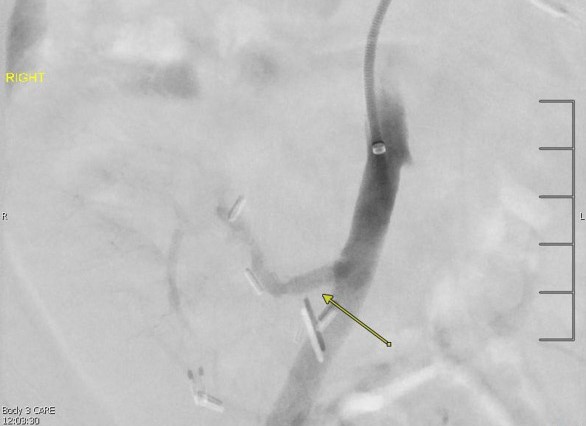

پروتئینوری در محدوده نفروتیک: نشانهای از رد حاد پیوند کلیه در بیمار مسن